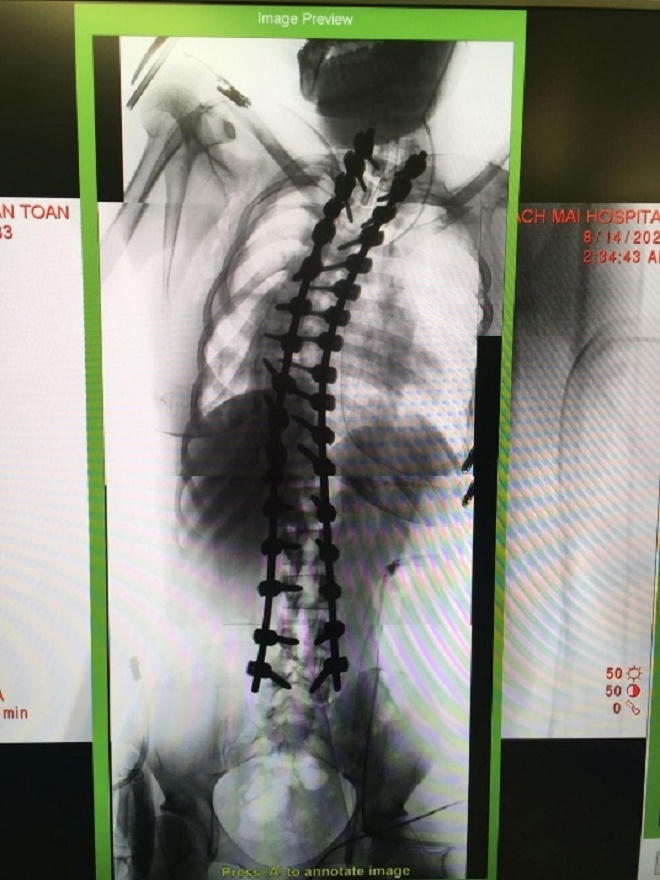

Trong quá trình phẫu thuật, đòi hỏi bác sĩ vừa phải đảm bảo sự an toàn cho người bệnh, tránh làm tổn thương thêm cho tủy sống, rễ thần kinh, mạch máu, lại vừa phải xử lý được tổn thương (thoát vị đĩa đệm, trượt đốt sống, dị dạng, u đốt sống, chấn thương). Đồng thời tái tạo cấu trúc sinh lý của cột sống bằng việc sử dụng vật liệu thay thế như: nẹp vít, ốc, đĩa đệm nhân tạo, nẹp silicon.

Phương pháp sử dụng hệ thống O-arm kết hợp định vị Navigation giúp cung cấp hình ảnh chính xác trong phẫu thuật cột sống. Đây là một giải pháp tiết kiệm thời gian trong phẫu thuật cung cấp hình ảnh độ phân giải cao 3D cho phẫu thuật viên và tự động đồng bộ hình ảnh trên hệ thống định vị Navigation. Đặc biệt Hệ thống O-arm và Navigation với không gian 3 chiều cho phép định vị chính xác vị trí cần phẫu thuật, giảm thiểu tai biến.

“Chỉ sai lệch 1-2mm trong quá trình phẫu thuật cột sống có thể khiến cho bệnh nhận bị liệt, tàn phế suất đời, thậm chí tử vong…”- BS CKII Võ Đức Chiến nhấn mạnh. Do đó, việc ứng dựng hệ thống O-arm giúp cho bác sĩ tiến hành được các ca phẫu thuật bệnh lý cột sống cho người bệnh an toàn, hiệu quả hơn vì hệ thống này cung cấp hình ảnh không gian 3D với độ phân giải cao, toàn diện giúp cho bác sĩ phẫu thuật biết rõ chính xác vị trí cần can thiệp tại cột sống, nhằm tránh ảnh hưởng các tổ chức xung quanh.

TS. BS Phạm Anh Tuấn, Trưởng khoa Ngoại thần kinh Bệnh viện Nguyễn Tri Phương cho biết: “Kĩ thuật phẫu thuật cột sống dựa trên hình ảnh chụp O-arm và hệ thống định vị Navigation giúp ca phẫu thuật cột sống có độ chính xác cao, tránh được các rủi ro và biến chứng cho bệnh nhân sau phẫu thuật”.

Việc sử dụng O-arm cùng với hệ thống định vị phẫu thuật, độ chính xác về vị trí bắt vít cột sống lên đến 93% - 100% so với tỷ lệ từ 72% - 92% của phương pháp thông thường. Hơn nữa, hệ thống này còn rút ngắn thời gian phục hồi của bệnh nhân, với bệnh nhân bị cong vẹo cột sống được thực hiện phẫu thuật bằng O-arm sau 3 ngày đã có thể đi lại được bình thường.